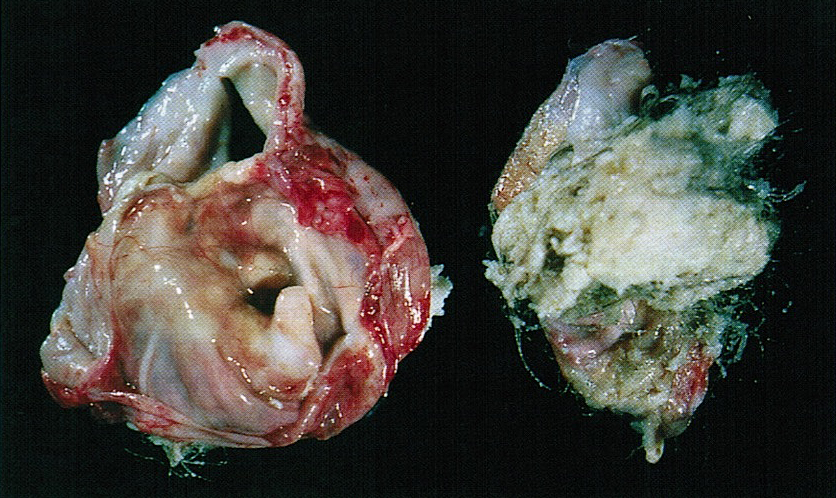

Gross description

- Smooth cyst that may contain hair, teeth, cartilage, bone or sebaceous material

- Generally < 10 cm

- Raised protuberance in cyst wall (Rokitansky nodule)

- Reference: StatPearls: Cystic Teratoma [Accessed 29 July 2021]

Gross images

D. Mature teratoma. The photo shows a mass with yellow sebaceous material and hair. In a 19 year old woman, this most likely represents a mature teratoma. Mature teratomas are the most common ovarian tumor and are especially common in women of reproductive age.